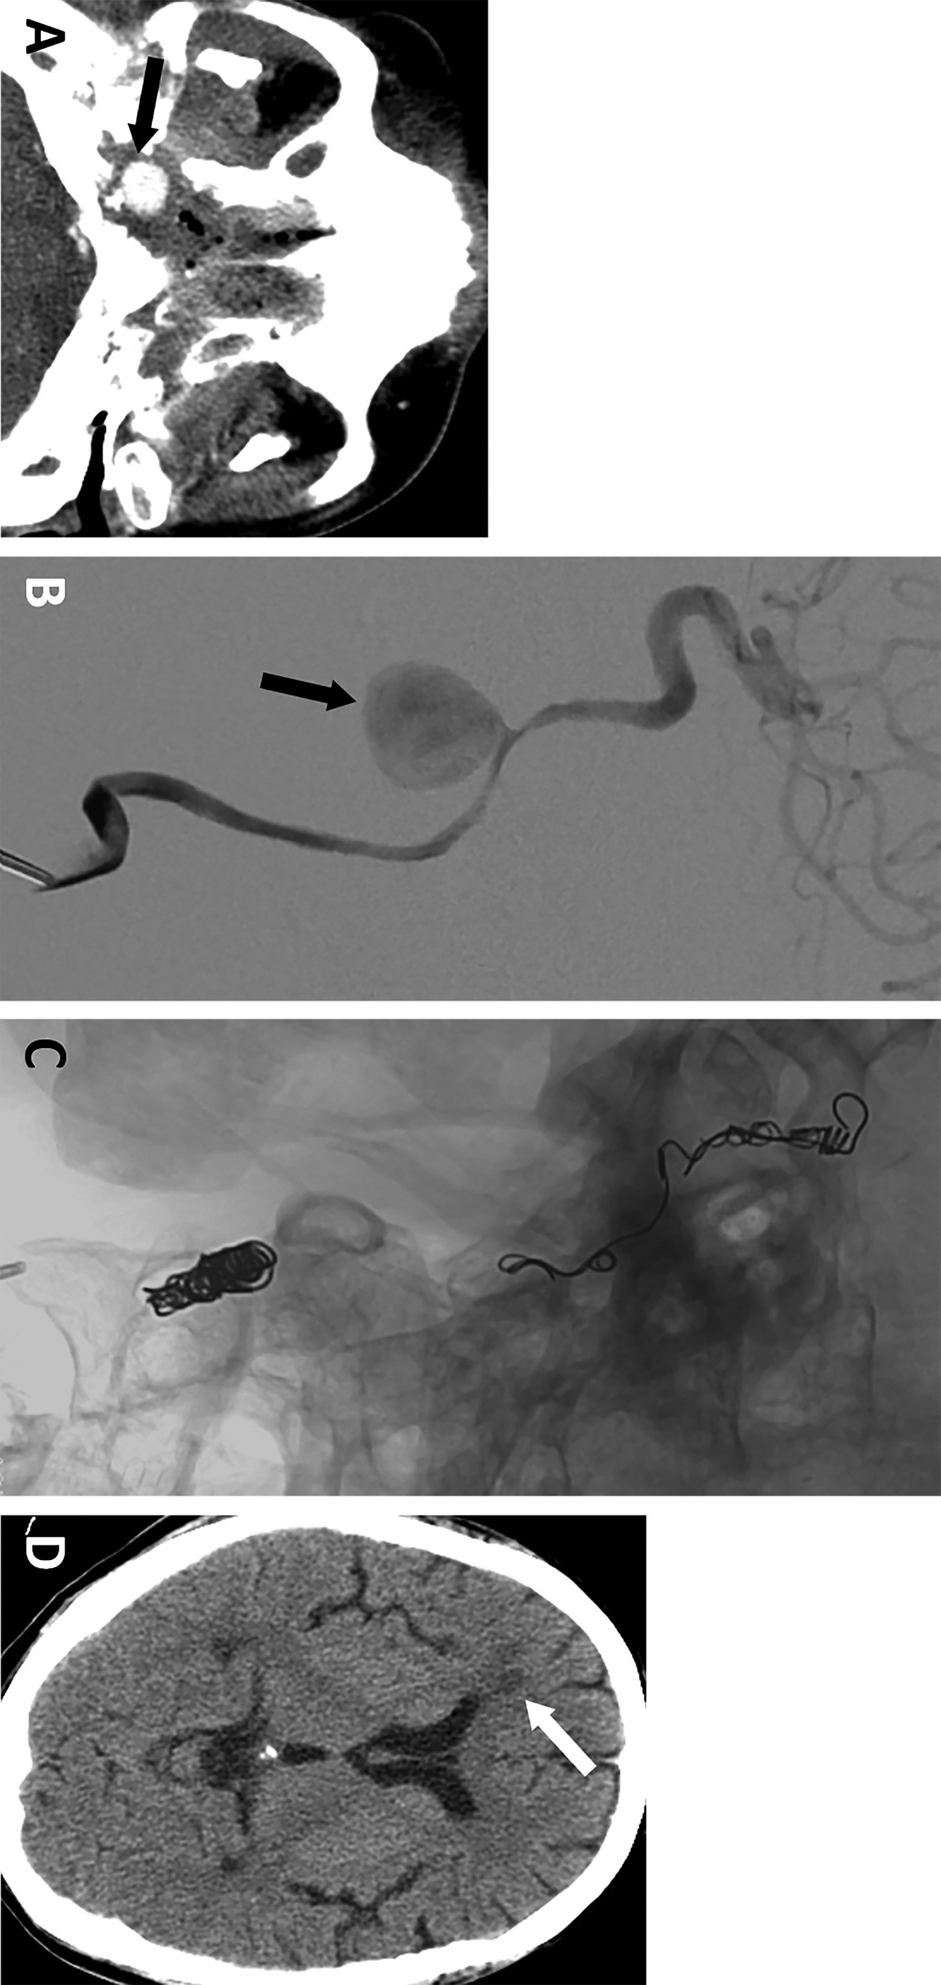

示例二. A,一名48岁右侧口咽癌男性患者,呕血及右侧鼻衄。CTA显示右侧岩段颈内动脉假性动脉瘤形成(箭头所示)。B,血管造影显示右侧岩段颈内动脉假性动脉瘤,无活动性出血(箭头所示)。C,右侧颈内动脉圈陷术后状态(采用可推入弹簧圈)。D,右侧颈内动脉圈陷术后2天颅脑平扫CT,显示右侧额叶白质新发梗死灶(箭头所示):